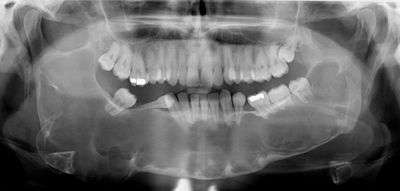

A keratocystic odontogenic tumour (also keratocystic odontogenic tumor, KCOT)[1] is a rare and benign but locally aggressive developmental cystic neoplasm. It most often affects the posterior mandible.

Swelling is the most common presenting complaint; however, KCOTs may be asymptomatic and found incidentally on dental X-rays.[5]

- Marsupialization - the surgical opening of the (KCOT) cavity and a creation of a marsupial-like pouch, so that the cavity is in contact with the outside for an extended period, e.g. three months.